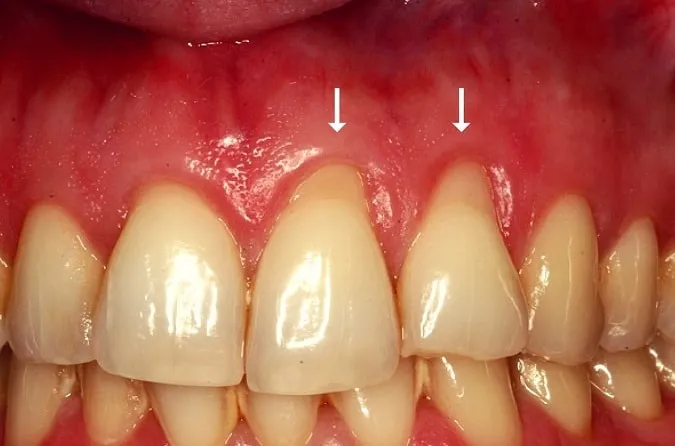

In the picture, the back teeth hit when moving sideways. The crown is too “fat” causing flexure. The gum has receded as a result of this, exposing the root. The root is softer and can be abraded by brushing. This can be restored with a gum graft and bite adjustment.

This case had recession most likely caused by the ligament between the teeth. A graft and minor surgical procedure corrected this.